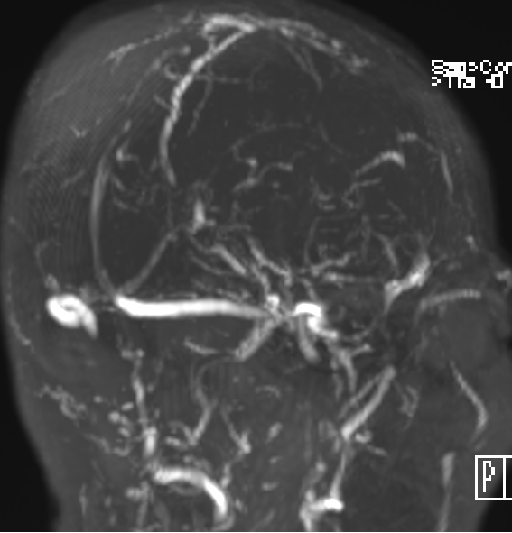

2015-1-30 DSA

脑压为60mm水柱

低颅压原因?(分流泵故障?脑顺应性差?

在局麻下行腰椎穿刺术+ 测脑压术,患者取左侧卧位,测量脑脊液压力为60mm水柱。